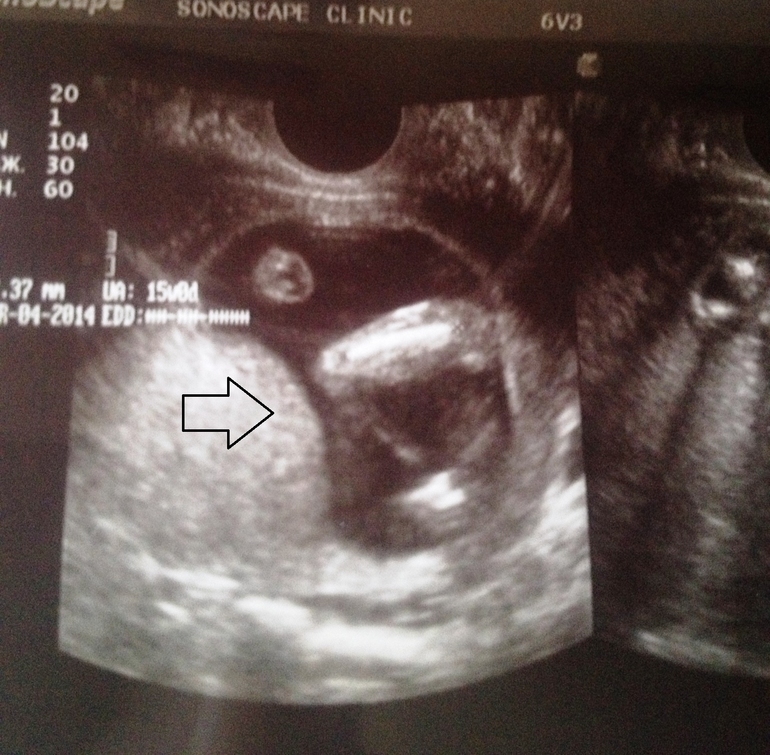

ТОнус, вчера вечером на узи подтвердили, думала може в кишечнике...да и что только не передумала...по задней стенке сильный тонус , видите на фото бугор.... это задняя стенка в тонусе ,давит на малыша